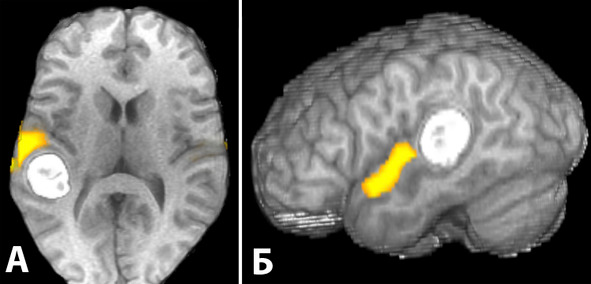

При функциональной МРТ оценивается гемодинамическая реакция в зависимости от активности нейронов при функциональной нагрузке (рисунок 19). Картирование этих зон позволяет визуализировать функционально значимые области и, в зависимости от их распространенности и смещения, помогает спланировать хирургический доступ. Исследование выполнено у 6 больных с поверхностно расположенными каверномами. В 4 случаях кавернома располагалась в пределах функционально значимой зоны, в двух – прилегала к функционально значимой зоне. Оценивалась активация ближайших функциональных центров: зона руки, зона ноги, зона Брока и зона Вернике. В связи с выраженными парамагнитными свойствами продуктов распада крови, во всех 6-ти случаях точно оценить близость зоны активации к каверноме было невозможно. Информацию о стороне расположения зоны активации по отношению к каверноме во всех случаях удалось использовать для планирования доступа. Таким образом, несмотря на ограничения метода (см. выше), его можно использовать, когда кавернома находится вблизи от функционально значимого коркового центра (таблица 20).

Рисунок 19. Трехмерная реконструкция МРТ больной с каверномой задних отделов верхней височной извилины слева. Наложена карта активации зоны Вернике (фМРТ, отмечена желтым).